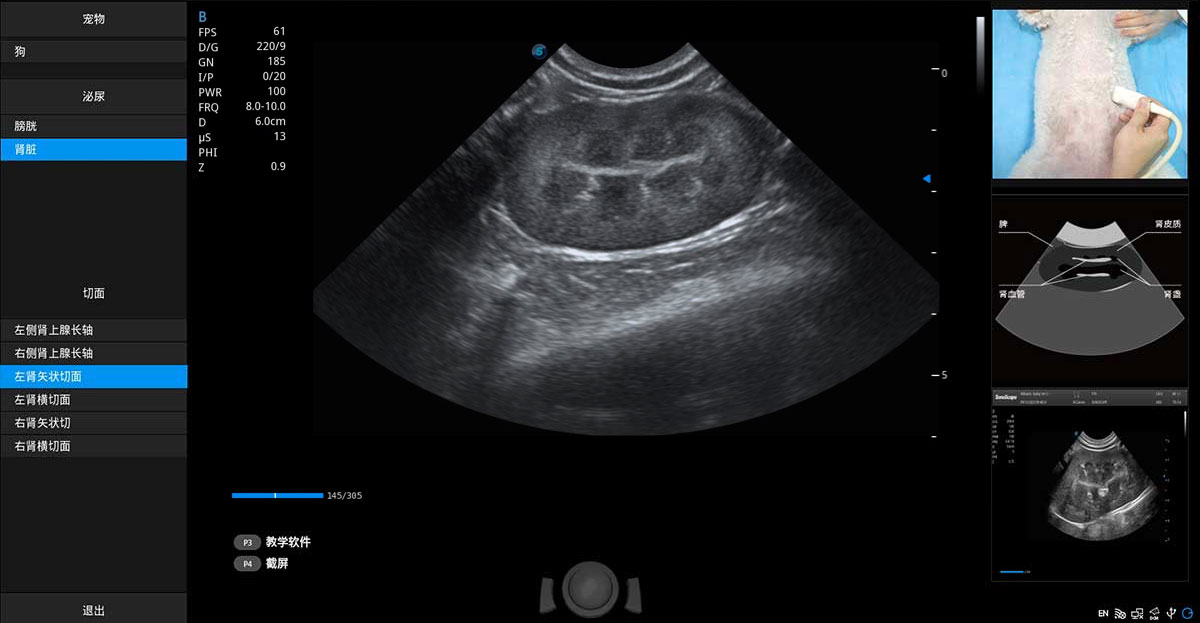

ProPet 70專為動(dòng)物醫(yī)生設(shè)計(jì),對(duì)不同的動(dòng)物體型和生理結(jié)構(gòu)作出了針對(duì)性的優(yōu)化。通過動(dòng)物影像專用軟件,可滿足個(gè)性化的應(yīng)用需求,幫助動(dòng)物醫(yī)生獲得更精確的診斷數(shù)據(jù)。

為精細(xì)結(jié)構(gòu)及組織邊緣提供高清晰度的圖像和更大的成像視野。幫助減輕醫(yī)生的用眼疲勞,快速精準(zhǔn)獲得測(cè)量的數(shù)據(jù)。

當(dāng)心臟測(cè)量結(jié)果超出正常范圍時(shí),可實(shí)時(shí)預(yù)警提示動(dòng)物醫(yī)生,減少疾病漏診概率。

提供解剖示意圖、標(biāo)準(zhǔn)超聲圖像、掃查手法圖和操作者實(shí)時(shí)檢查圖像,指導(dǎo)操作者進(jìn)行標(biāo)準(zhǔn)切面的正確掃查。